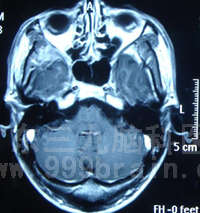

调强计划矢状位上靶区剂量 调强计划冠状位上靶区剂量

肿瘤空间位置示意图(箭头位置) 肿瘤三维重建示意图(箭头位置)